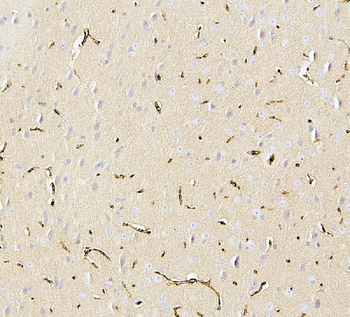

100 μg - PGP9.5 antibody [orb6713]Featured

ELISA, ICC, IF, IHC-P, WB

Human, Mouse, Rat

Rabbit

Polyclonal

Unconjugated